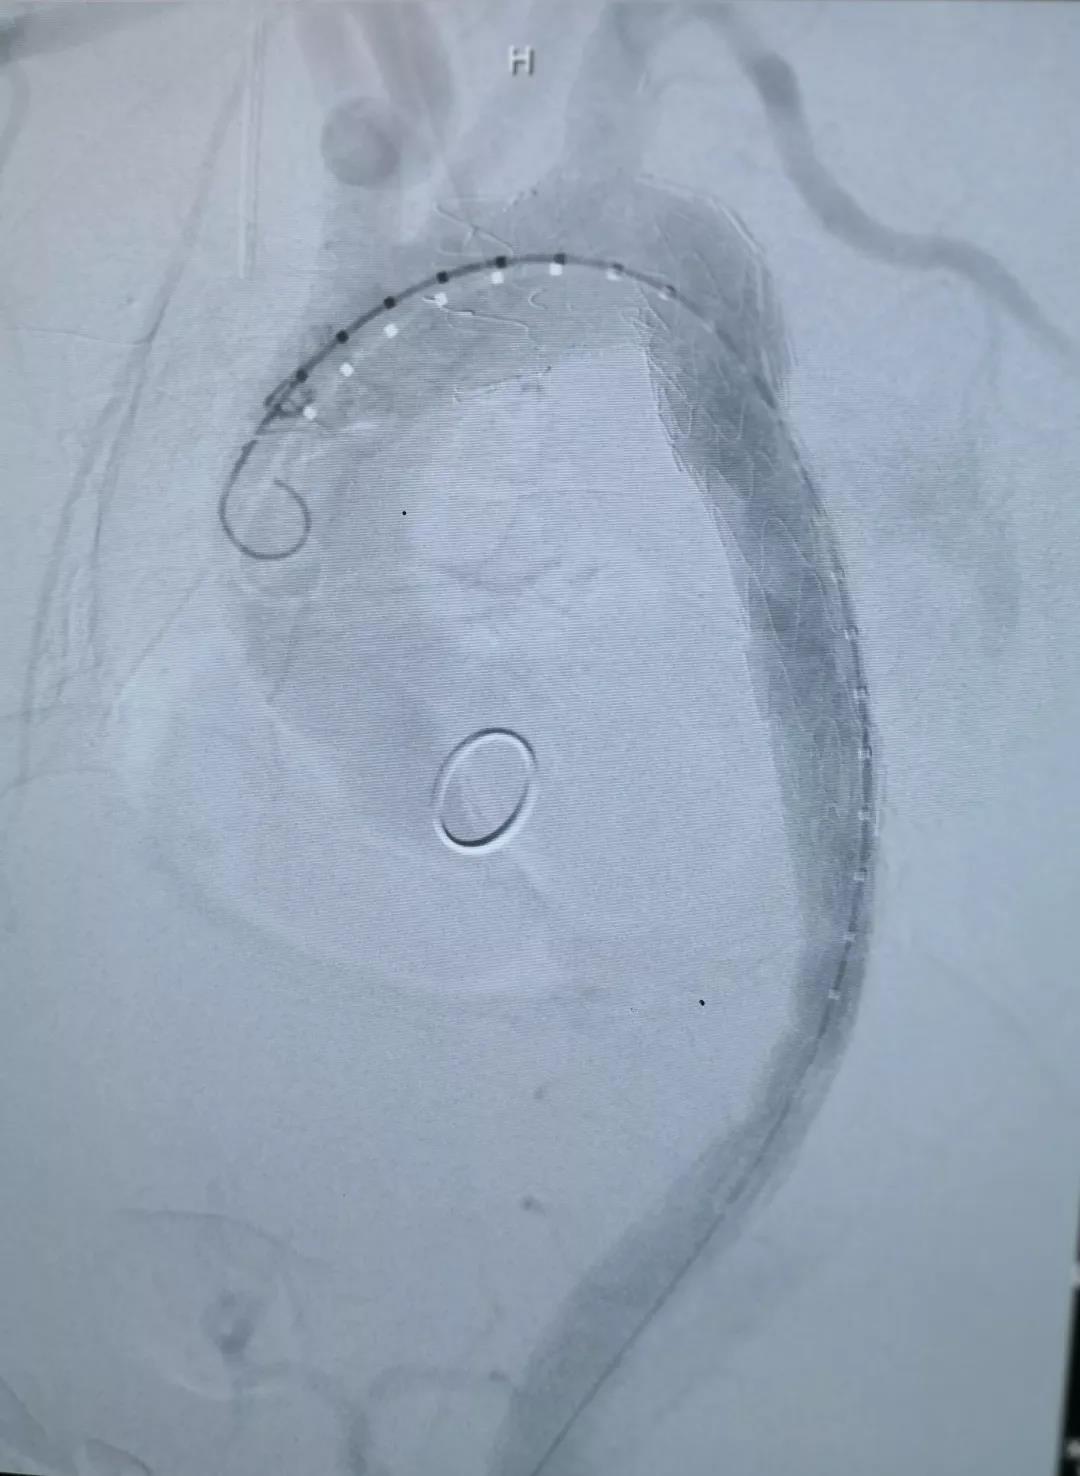

术中通过DSA造影显示:主动脉夹层破口位于左锁骨下动脉近端,真腔压闭。舒畅教授通过左锁骨下动脉预置Longuette™裙边支架,释放 Ankura™ Pro主动脉主体覆膜支架,封堵破口后通过裙边支架显影点准确定位,释放裙边支架,凭借着舒畅教授精湛的手术操作和器械的优异性能,手术过程非常顺利,胸主动脉支架释放良好,患者的主动脉夹层破口封闭良好,左锁骨下动脉释放的裙边支架血流通畅,没有内漏发生。由于患者远端真腔较小,为了保证远端的血流,植入了一个cuff支架,造影显示远端真腔打开良好。

(图:术后造影)

手术结束后的现场提问环节中,舒畅教授在回答关于术式选择的问题时讲到:由于患者破口很大,不适用于体外开窗的方式;且患者左锁骨下动脉相对比较扭曲,与主动脉弓有成角,采用原位开窗的方式比较困难,因此选择了平行支架(即烟囱)的方式进行处理。此病例选择的先健Longuette™裙边支架,其独特的外柔内刚的设计,可巧妙的解决烟囱技术中的内漏问题。同时,舒畅教授还提到,Longuette™裙边支架共有4个显影点,DSA下显影良好,可确保术中精准定位。同时,Longuette™支架的内层结构相对裙边适度加长,适宜的长度可在防止大支架将分支支架遮蔽的同时保证分支支架不遮挡左颈总动脉。先健新型主动脉支架系统在防堵、防漏、防疲劳方面都进行了周全的考虑,是主动脉疾病的腔内治疗在主动脉弓部方向上的创造性突破。